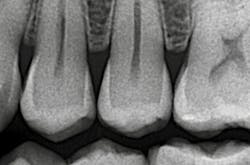

Although the radiographic appearance of these restorations is somewhat unfamiliar, they show long-term success (figures 4a–4b).

Figures 4a and 4b: Radiographic appearance and four-year follow-up of minimally invasive Class II tunnel cavity preparation on tooth 12D